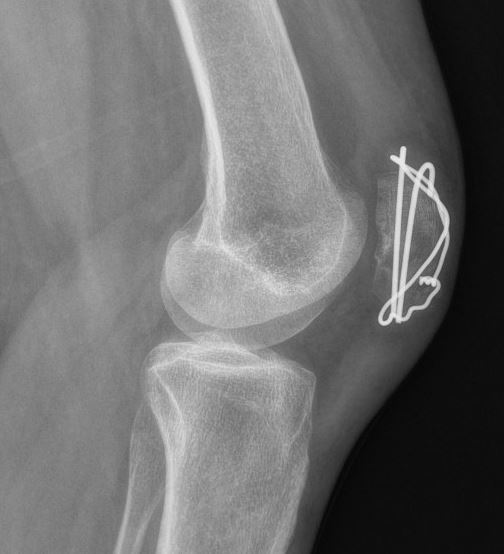

De meeste breuken van de knieschijf zullen operatief vastgezet moeten worden met een zogenaamde ‘Zuggertung’, bestaande uit enkele dunne metalen pinnetjes en een metalen vlechtdraad om de knieschijf heen. Soms worden er ook schroeven gebruikt. Het materiaal wordt geplaatst via een snede aan de voorkant over de knieschijf.

Zoals elke operatie, heeft ook een operatie voor een gebroken knieschijf kans op complicaties, zoals nabloedingen en ontstekingen van de wond, doofheid van de omliggende huid, het loslaten van het fixatie materiaal en het niet goed willen vastgroeien van de breuk. Ook hebben patiënten na een operatie nogal eens last van irritatie van het fixatiemateriaal, omdat het materiaal hier vlak onder de huid ligt. Indien de breuk weer op volledige sterkte is (meestal pas na circa 9-12 maanden) en het fixatiemateriaal geen nut meer heeft, kunt u overwegen om het materiaal weer operatief te laten verwijderen indien u hier klachten van hebt. Indien u geen klachten hebt, kunt u het fixatiemateriaal veilig laten zitten.